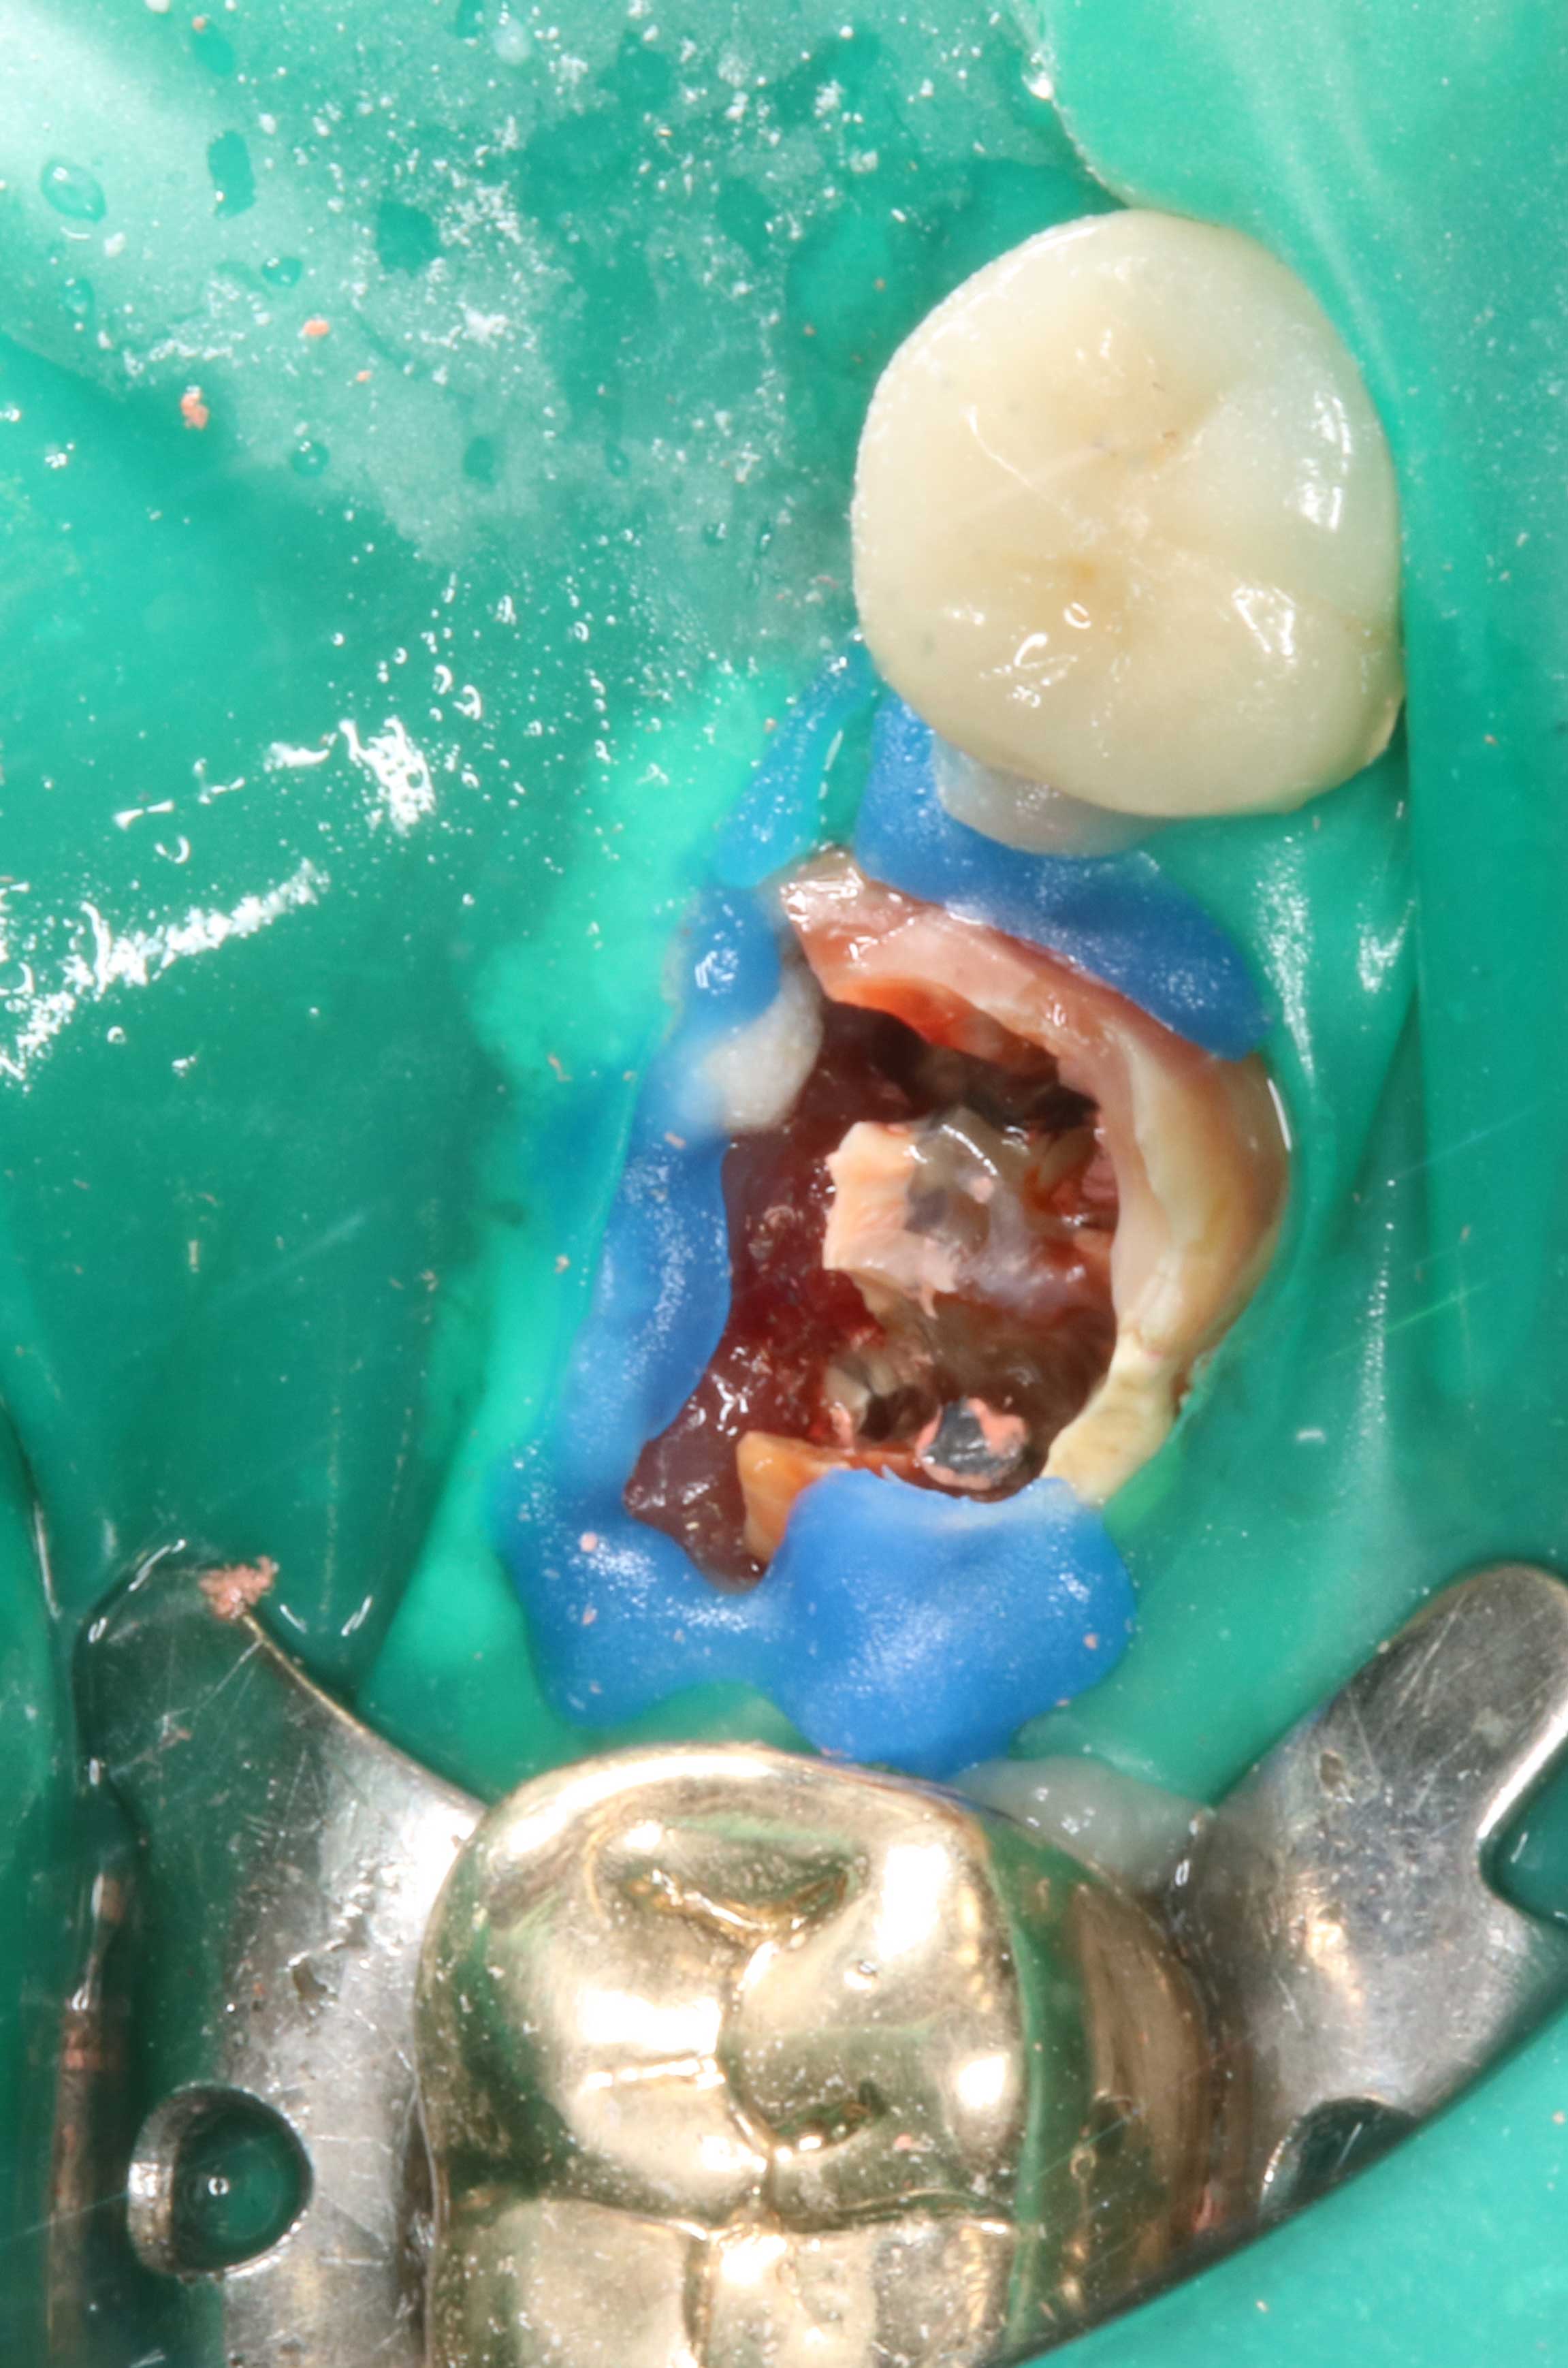

Endo

Endodontie

Kofferdam

Wurzelkanalbehandlung